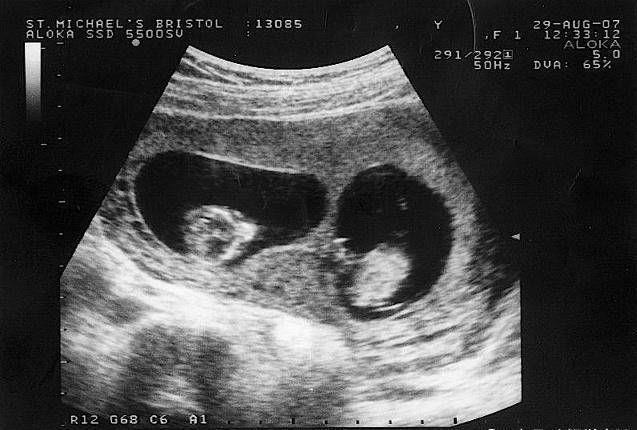

打胎:一般来说当夫妻没有要宝宝的打算时,出现意外怀孕的时候在需要通过一些医疗方式来停止妊娠,也就是我们所说的打胎。医生建议,最好在在宝宝没有满三个月以前,可以通过引产的方式将腹中的胎儿给打掉。